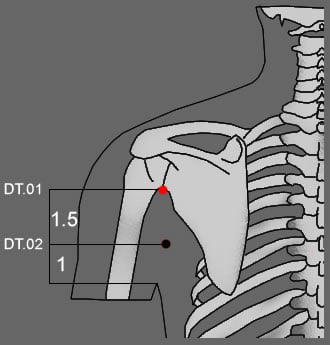

מיקום

בלחי האחורית של האקסילה, בחיבור של הסקפולה עם ההומורוס.

1.5 – 1 צון.

הנקודה ממוקמת על ערוץ ה- Tai Yang של היד.

ראה: Dt.02